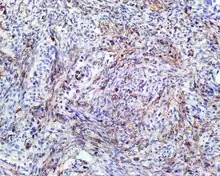

- S100 protein (a tumor marker protein) is focal, patchy to diffuse in all tumors.

S100 protein reaction in a biphenotypic sinonasal sarcoma - Smooth-muscle actin or muscle-specific actin is seen in nearly all tumors, but a strong and diffuse reaction with SMA is seen in only about 50% of cases.

Smooth-muscle actin reaction in a biphenotypic sinonasal sarcoma - No reactivity occurs with other tumor markers such as SOX10, myogenin, estrogen receptor, progesterone receptor, or keratins.